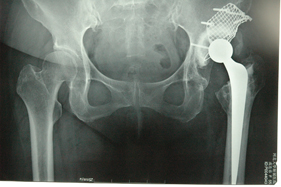

rivision total hip replacement for dislocation and severe bone defect

(post-op)rivision total hip replacement for dislocation and severe bone defect

lateral view of left hip

anterior-posterior view of left hip

anterior-posterior view of bilateral hips